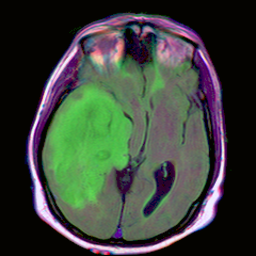

The following example uses the U-Net for brain segmentation model trained to detect lower-grade gliomas to demonstrate how to:

input_image = Image.open("./data/TCGA_CS_4944.png")

display(input_image)